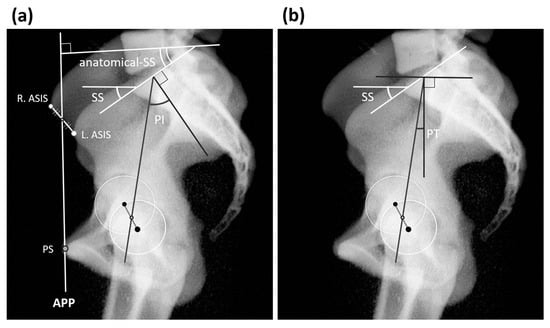

2.2. Measurement of Pelvic and Spinal Parameters

| APPA | −6.8 ± 9.3 | −0.8 ± 6.9 | −3.9 ± 8.8 | −7.3 ± 7.9 | −13.3 ± 9.4 |

| SSx | 35.5 ± 9.0 | 38.0 ± 7.9 | 36.9 ± 7.9 | 35.8 ± 8.9 | 32.5 ± 10.7 |

| PTx | 16.3 ± 7.3 | 12.9 ± 6.9 | 14.7 ± 7.4 | 16.1 ± 5.7 | 20.6 ± 8.1 |

| PI | 52.0 ± 10.0 | 50.9 ± 9.8 | 51.5 ± 10.4 | 52.5 ± 9.1 | 53.3 ± 10.9 |

| a-SS | 42.4 ± 10.4 | 38.9 ± 10.0 | 40.8 ± 9.7 | 43.6 ± 9.8 | 45.6 ± 11.5 |

| a-PT | 9.6 ± 7.8 | 12.1 ± 6.6 | 10.8 ± 8.0 | 8.9 ± 7.6 | 7.6 ± 9.0 |